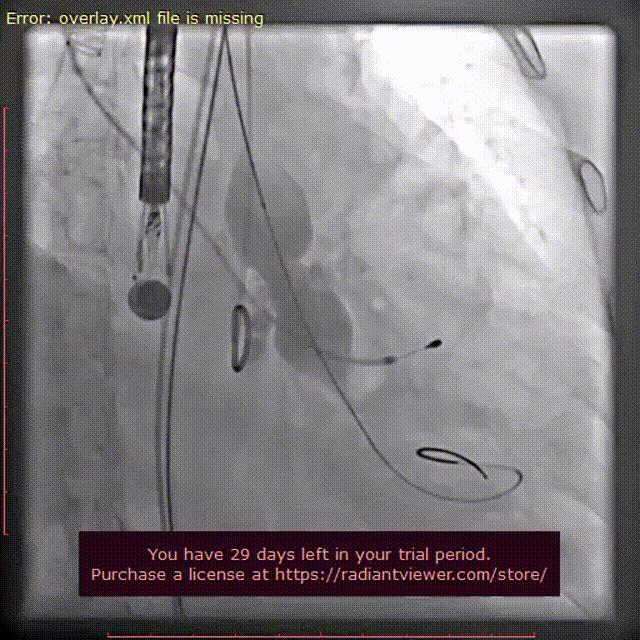

TaurusElite输送系统顺利过弓跨瓣后,AV26瓣膜瓣环上4mm定位释放,到工作位后造影显示位置良好,但受钙化影响有中量瓣周漏。随后进行回收,瓣环上6mm再次定位释放。

瓣膜初次释放至工作位

瓣膜再次释放至工作位